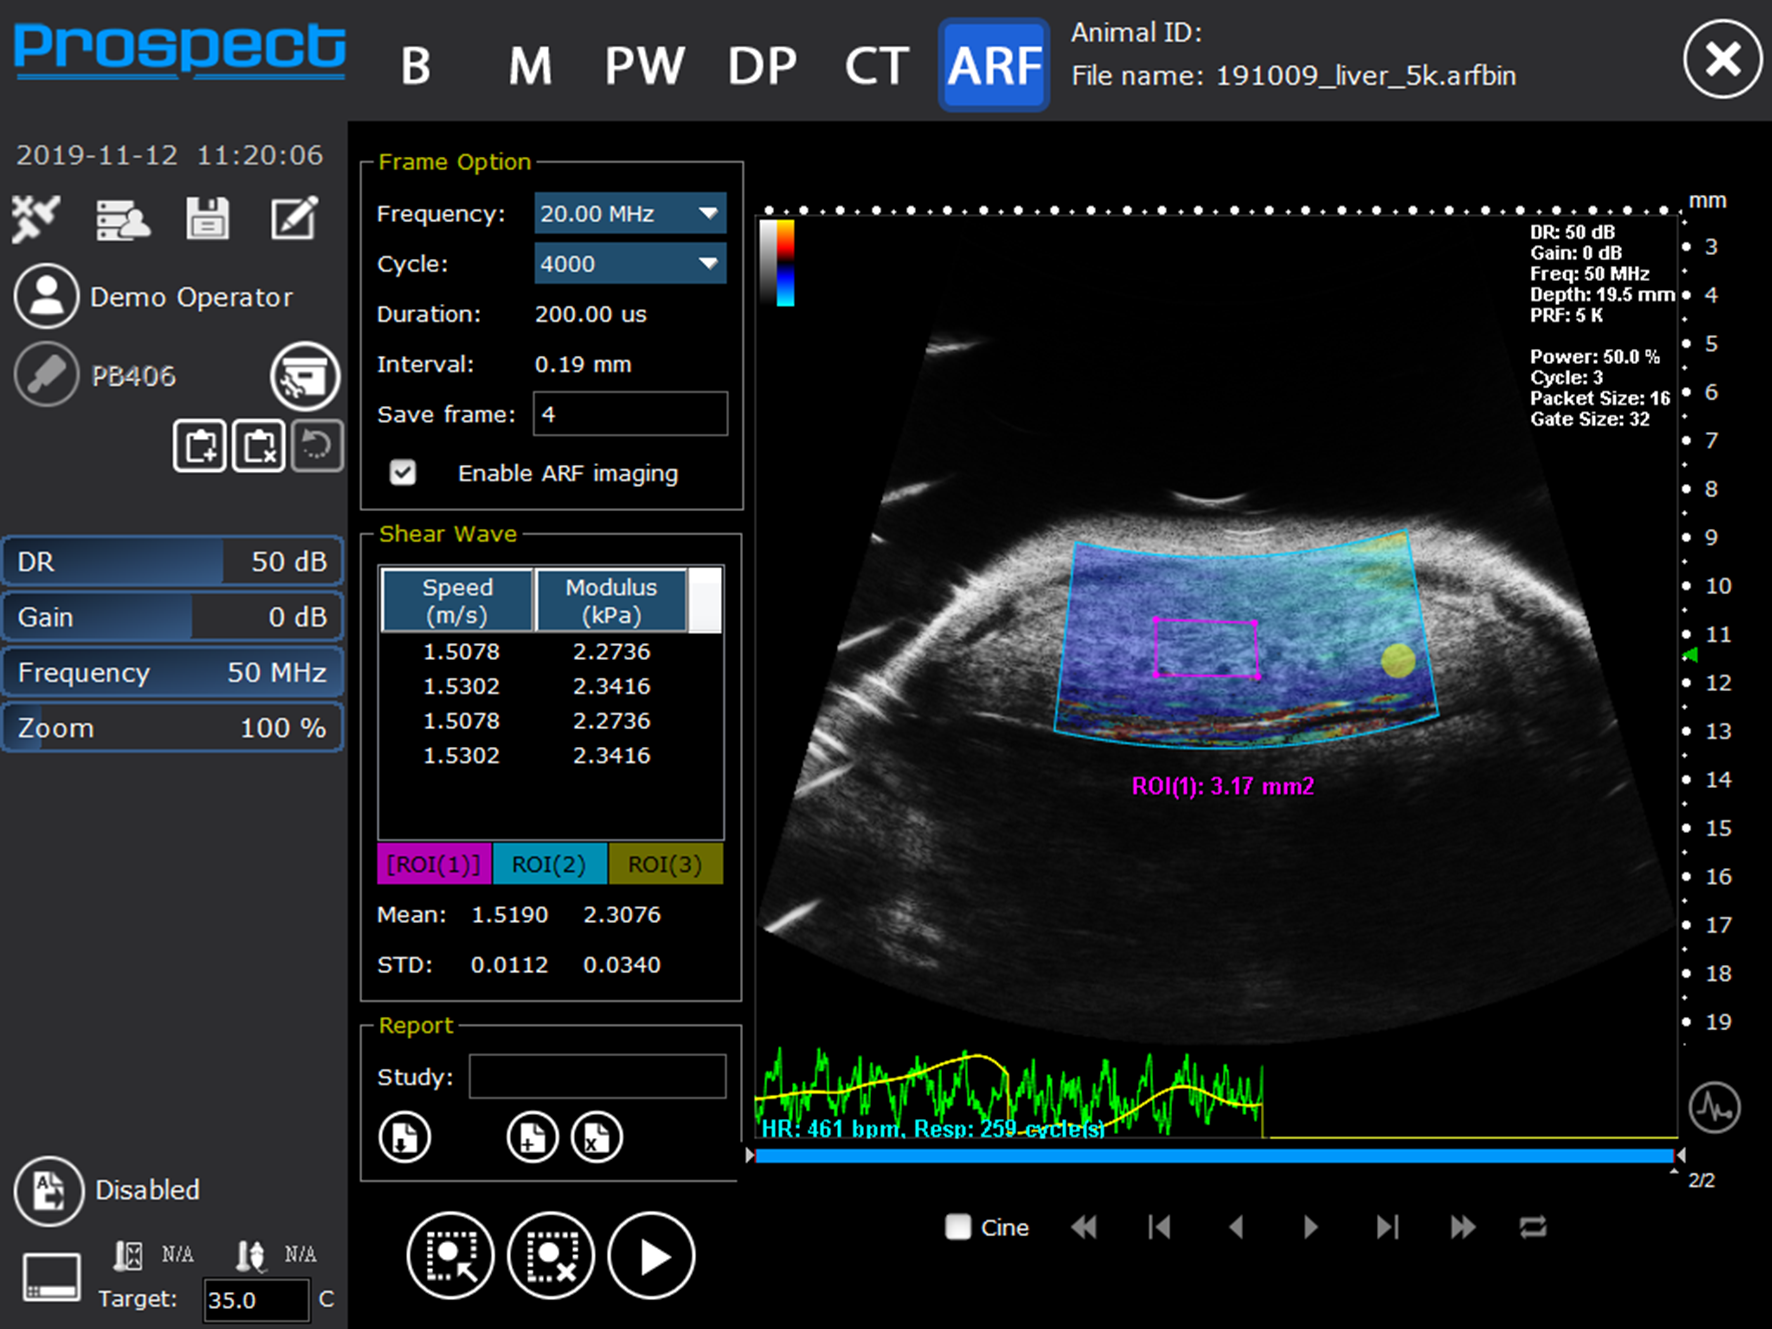

Alternatively, the measurement of shear wave velocity enables a quantitative measurement of Young's modulus of elasticity, E, provided that the tissue can be assumed to be incompressible (no change in density) and uniformly elastic (Figure 8). The shear modulus G is related to the Young's modulus of elasticity E, by the following equation. E = 3G. Shear wave velocity, cs, generated as a result of a shearing force is given by, cs = √(G/ρ). By measuring the shear speed (usually between 1 and 10 m.s−1) and knowing the density, ρ, of the soft tissue (estimated at 1,000 kg.m−3), Young's modulus of elasticity can be calculated from the equation E = 3ρcs2. Hence measuring the shear speed can provide quantitative information on the elastic modulus. More detailed information on elastography techniques can be found in Hoskins [5] and Bamber et al. [6].

FIGURE 8

www.frontiersin.org

Figure 8. Shear wave elastography image of liver showing mean shear wave velocities and Young's modulus from a mouse liver (Reproduced with permission from S-Sharp Corporation).

Preclinical Ultrasound—Liver Applications

The liver is a large organ within the mouse and consists of four lobes. To image the mouse liver, the mouse is again scanned in the supine position using insonating frequencies between 30 and 40 MHz (Figure 15). B-mode ultrasound can be used to image all 4 lobes of the liver while ultrasound enables the portal vein and hepatic artery to be identified and blood velocities measured. Identification and sizing of tumors; staging of non-alcoholic fatty liver disease [21] and determination of fibrosis in the liver can also be achieved at preclinical frequencies. For the assessment of fibrosis in the liver, shear wave imaging techniques can also be used to measure the viscoelastic properties of mouse liver (Figure 8) [22]. For preclinical imaging applications, shear waves are generally generated by a lower frequency 20 MHz radiation pulse and a 40 MHz probe used to measure the shear wave propagation within the liver tissue.